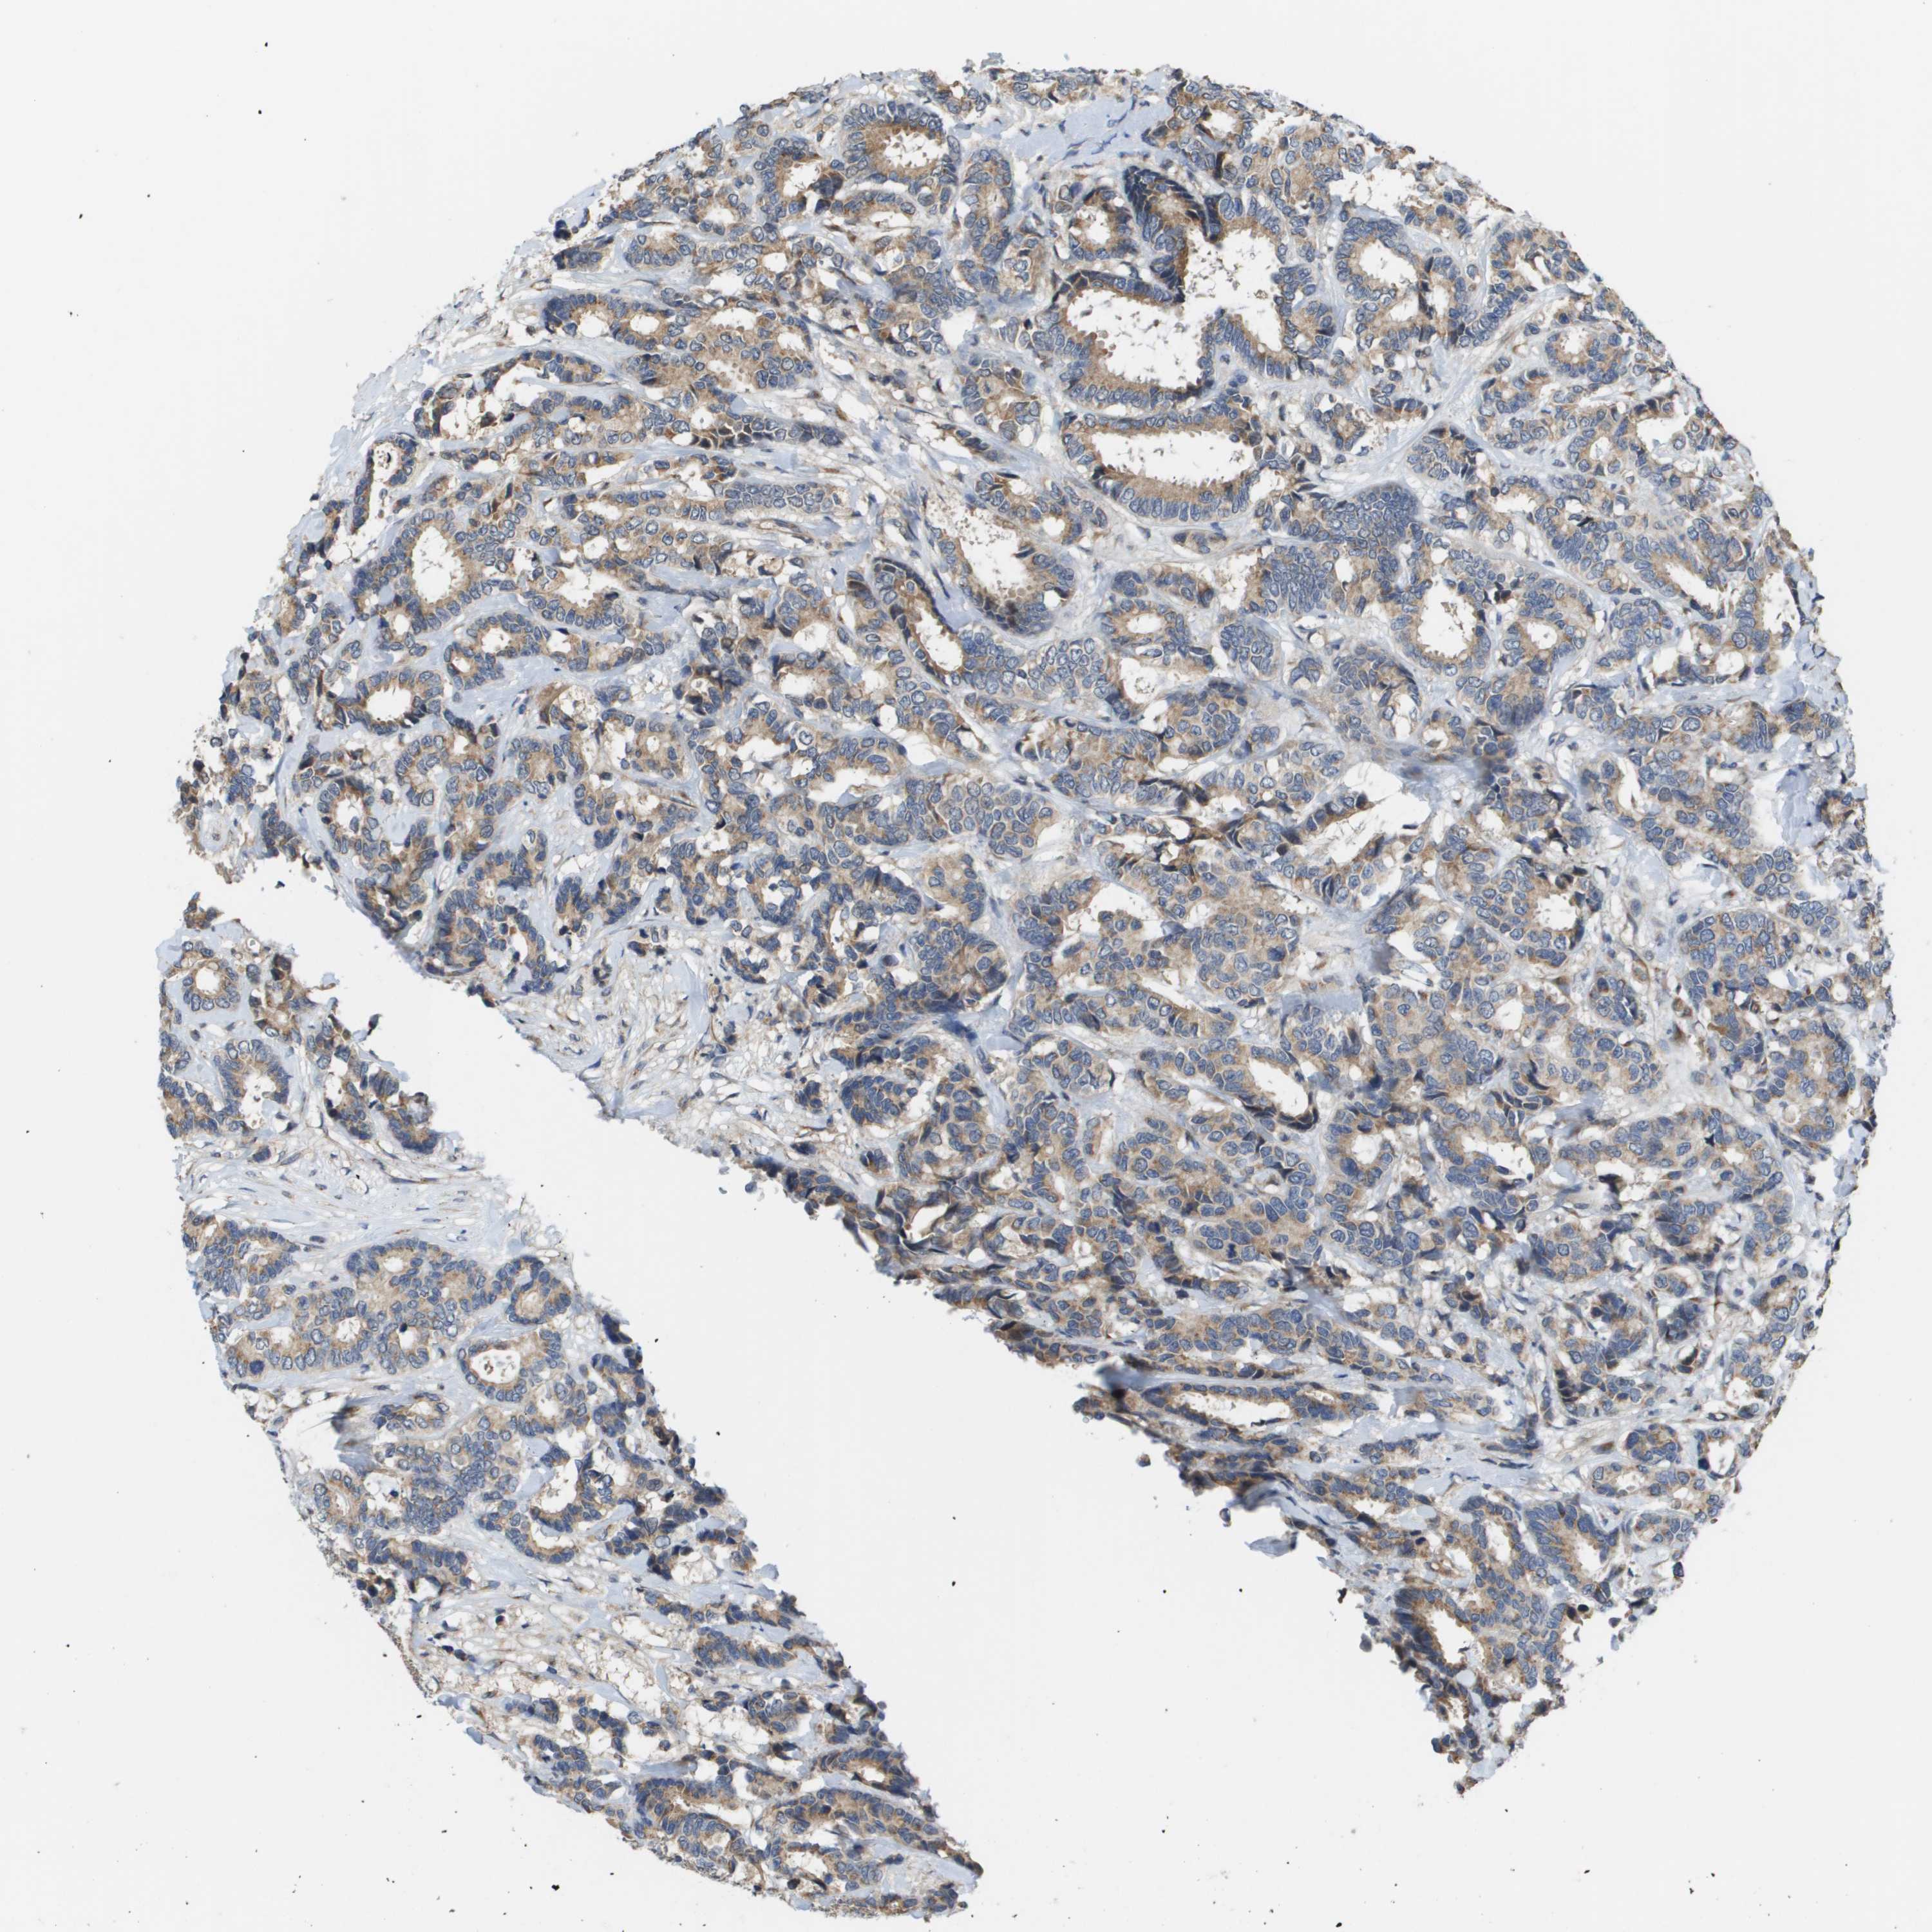

CANCER BREAST CANCER Show tissue menu

BRCA TCGA BRCA VALIDATION PROTEIN EXPRESSION